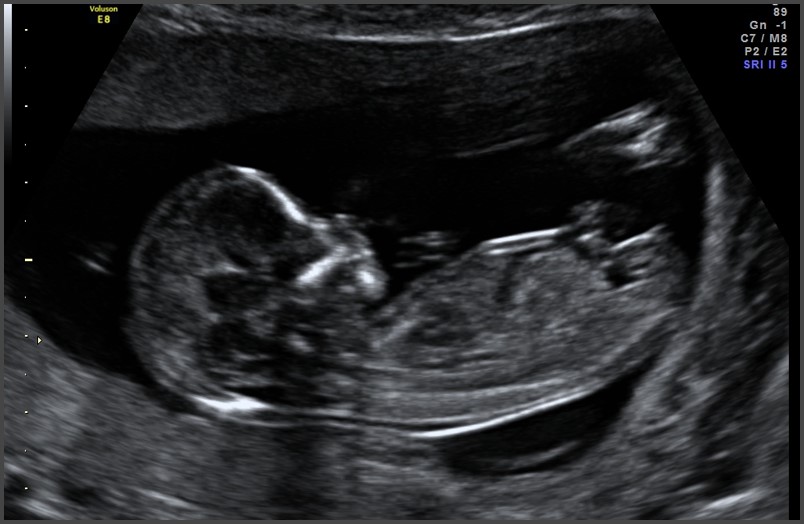

Llegó el momento de la ecografía de detalle anatómico. Esta tiene como objetivo examinar con detalle todos los órganos y sistemas fetales. A través de la valoración ecográfica del cerebro, la cara, corazón, pulmones, diafragma, estómago, intestinos, riñones, vejiga, columna, brazos, antebrazos y manos; se puede hacer el diagnóstico de malformaciones fetales. Permite establecer el pronóstico y el tratamiento de algunas enfermedades fetales susceptibles de intervención en el útero, evaluar alteraciones en el líquido amniótico y la placenta. Permite además descartar la presencia de algunos signos ecográficos que sugieran la presencia de enfermedades genéticas como síndrome de Down. En el caso de diagnosticarse alguna malformación, se comenta con los padres el significado y el pronóstico, si es necesario ampliar el estudio con más exámenes, pruebas genéticas en muestra de líquido amniótico, ecografía de corazón (ecocardiograma), ecografía del cerebro (neurografía) o imágenes adicionales como resonancia magnética.

Ecografía de tamizaje genético: aunque puede realizarse entre las semanas 11 a 14, el mejor momento para hacer la ecografía de tamizaje genético es la semana 12. El tamaño actual del bebé permite determinar si la mayoría de órganos se estén desarrollando de manera adecuada. Esta ecografía en manos expertas puede detectar hasta el 60% de las malformaciones mayores que se pueden presentar durante el embarazo.

Uno de los parámetros más importante es la medición de la nuca del bebé conocida como translucencia nucal, que corresponde al líquido que todos los fetos tienen en la parte posterior del cuello. El grosor de la nuca del feto se utiliza para establecer el riesgo de síndrome de Down. Para calcular este riesgo se combina la medida de la nuca con tu edad, la presencia de soplo en el corazón, la forma en que palpita una vena que llega al corazón conocida como ductus venoso y los valores de dos hormonas (BHCG y PAPP-A) que se obtienen mediante una muestra de tu sangre.

Esta ecografía también permite establecer el riesgo de otras posibles complicaciones del embarazo como el parto prematuro, la preeclampsia (presión alta durante el embarazo) y la restricción del crecimiento fetal (bajo peso del bebe durante la gestación). En caso de identificar alto riesgo de preeclampsia tu médico te formulará 150 mg de ácido acetil salicílico cada noche y calcio para disminuir la probabilidad de que esto ocurra.